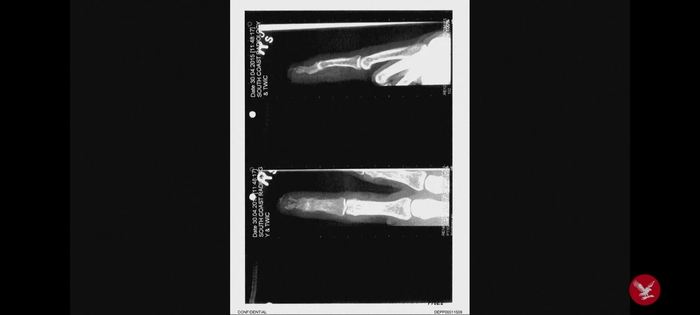

Доктор Гилберт говорит, что его привлекли к этому делу, чтобы просмотреть медицинскую документацию Деппа относительно его травмы пальца и составить мнение о том, могла ли она быть получена описанными способами.

Врач подтверждает, что ему известно о том, как Депп получил травму - бутылкой водки, брошенной Херд, - и о ее версии, что он мог порезать палец, разбив телефон о стену.

Он сказал, что, по его профессиональному мнению, рана была нанесена "резким разрывом", основываясь на снимках, сделанных сразу после травмы. Он добавил, что источником этой рваной раны могла быть бутылка водки. Доктор Гилберт говорит, что бутылка свободно могла и раздавить кончик пальца и, из-за скорости полёта, разбиться и отсечь кончик. Крайне редко можно встретить такую травму при просто переломам и драках.

Что касается описания причины, сделанного Херд, он сказал, что это "крайне маловероятно", Если бы он бил телефоном об стену, точно пострадали бы костяшки пальцев, маловероятно - кончик.

— Почему вы считает, что способ получения травмы может совпадать с описанием Деппа?

— Его рука свисала с барной стойки. Бутылка разбилась, что привело к тому, что мягкие ткани повредились.

Доктор отрицает, что просто при ударе или даже гвоздём в стене можно получить такую травму.

Он говорит, что столешница была мраморная, палец под углом, бутылка тяжёлая, плюс она может стать реже-колющим предметом - все сходится.

Также доктор Гилбер прокомментировал рентгеновские снимки. Доктор Гилберт добавляет, что кончик пальца был отсечен очень ровно, для таких травм нужна острая поверхность и на скорости, ибо отсечено до кости. При такой глубокой ране, если бы это был обычный удар, кожа и ткань были бы разорваны неровно. Говорит, что силы удара летящей бутылки с такого расстояния хватило бы для такого повреждения.

Также он указывает на то, что вокруг раны Деппа не было царапин и осколков стекла. Доктор Гилберт говорит, видел много порезов от стекла, часто такое остаётся от бокалов. Когда порез от бутылки , там стекло толще и не разбивается на такие мелкие кусочки, толстое стекло бьется на большие части.

Также доктор повторяет, что если бы травма бы следствием удара об стену, то был бы поврежден не один палец, а на руке не было ни других повреждений, ни синяков.

Доктор Гилберт согласился с выводом доктора Мура о том, что невозможно "определенно" сказать, чем была вызвана травма.